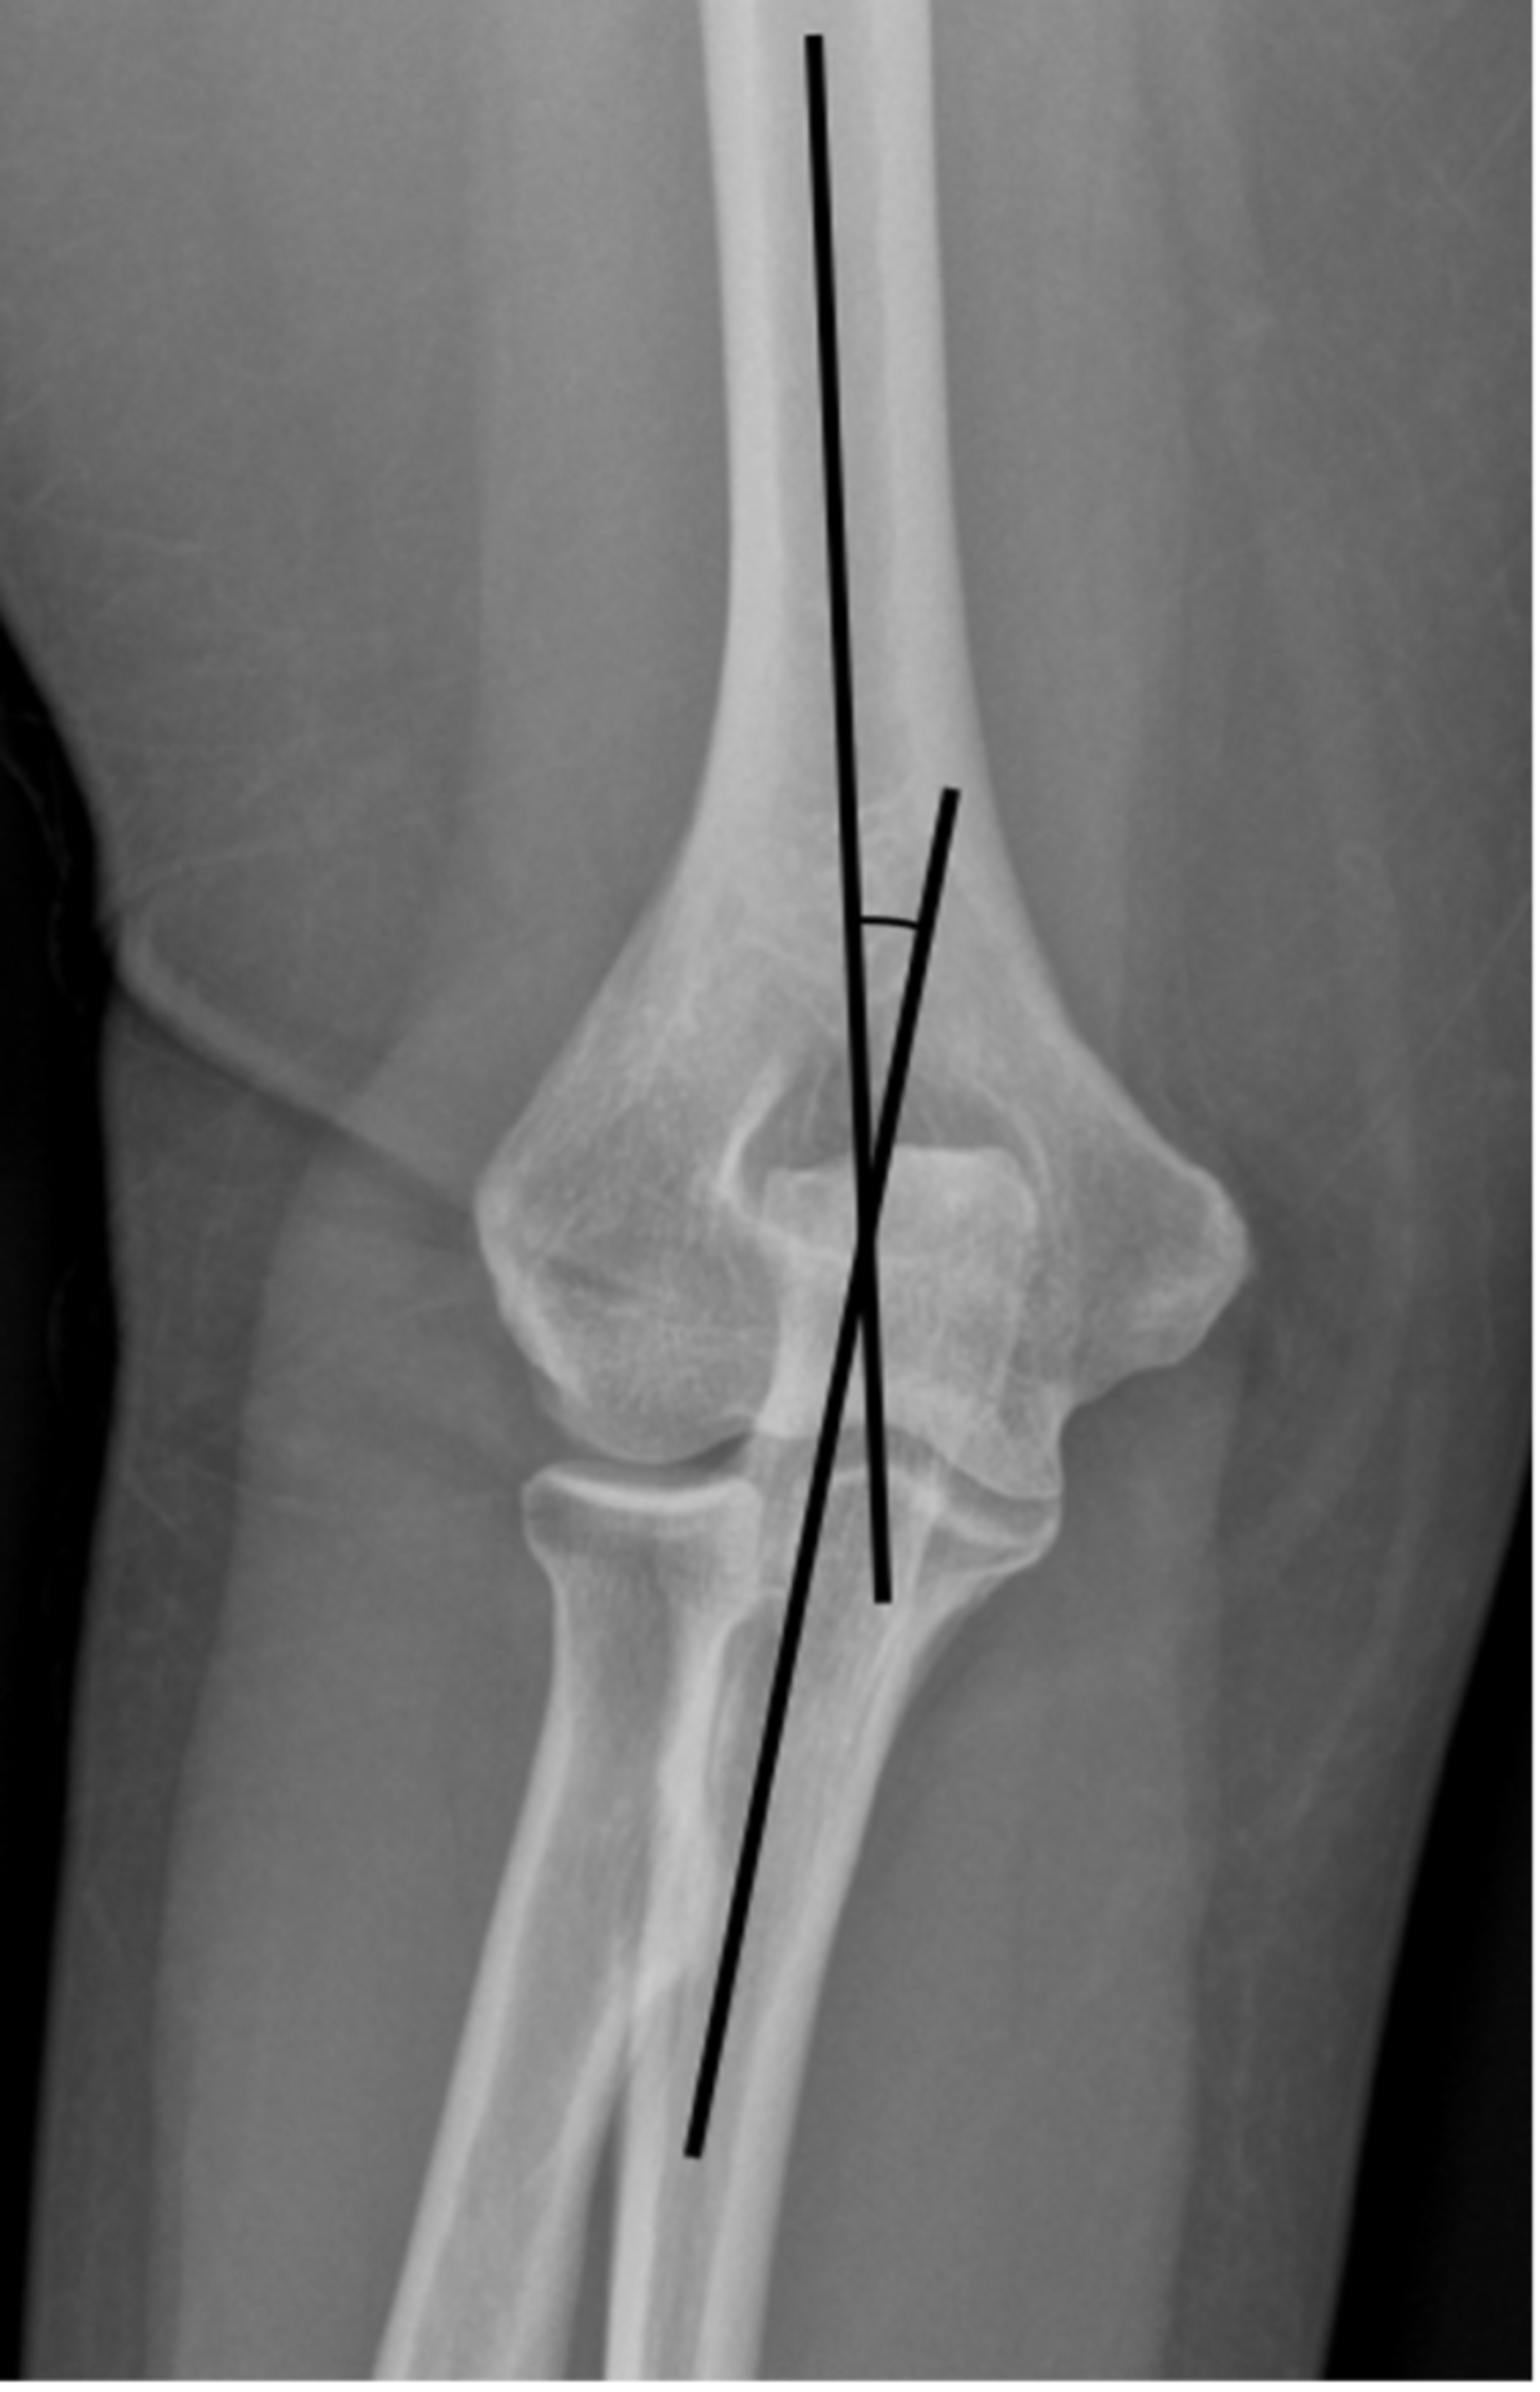

How To Measure Carrying Angle Of Elbow At Home . carrying angle is measured by a manual goniometer with two drawing axes of the arm and forearm. the carrying angle of elbow is a natural anatomical feature that describes the angle between the upper arm and forearm when. understanding the carrying angle can provide insights into joint stability, mechanics, and potential deviations that may occur. the carrying angle is defined as the angle made by the arm's median axis and forearm [3], which is fully extended and supinated and measures the. the carrying angle of the elbow is the clinical measurement of. The axis of the arm is defined by the lateral border of the. carrying angle is a small degree of cubitus valgus, formed between the. how to measures and normal values?#hazem_hamed_radiology

the carrying angle is defined as the angle made by the arm's median axis and forearm [3], which is fully extended and supinated and measures the. the carrying angle of the elbow is the clinical measurement of. carrying angle is a small degree of cubitus valgus, formed between the. The axis of the arm is defined by the lateral border of the. understanding the carrying angle can provide insights into joint stability, mechanics, and potential deviations that may occur. how to measures and normal values?#hazem_hamed_radiology carrying angle is measured by a manual goniometer with two drawing axes of the arm and forearm. the carrying angle of elbow is a natural anatomical feature that describes the angle between the upper arm and forearm when.